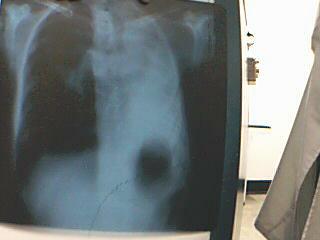

10分钟前拍一胸片因是普通x光故未能上传,患者45岁女,身体虚弱,自述18年结核病史,x光片见右肺上野有3处高密度影边缘不清,大概2*2cm问题在于左肺什么都没有什么也看不见,全部呈现透光样,右心缘消失,双隔上提,左肋隔角消失,右肋隔角变钝隔面不光滑,现在请各位给点建议,问题的关键是左面什么都看不见.

相机没点~勉强用视频拍的

左胸廓缩小,纵隔气管对称性左移,左肺野大片致密影,胃泡上移;右肺代偿性气肿。提示左肺不张,纵隔疝,左侧胸膜肥厚粘连。建议ct检查。

左肺不透明,纵隔心影左移,胃泡上移,左膈、左肋角无显示。结合18年的结核病史。考虑左肺毁损伴左侧广泛胸膜增厚粘连。

左胸廓国对侧塌陷,左肺不透明,纵隔心影左移,胃泡上移,左膈、左肋角无显示。结合18年的结核病史。考虑左侧肺不张、广泛胸膜增厚粘连。

胃泡影上提,左肺野大片状阴影,肋骨间隙变窄,气管纵隔影左移,右肺代偿性气肿。提示:纵隔疝,左侧毁损肺。

左侧肺野密实,心影纵隔左移,胃泡上移,左膈面显示不清。拟诊:左肺毁损伴左侧广泛胸膜增厚粘连。

中线结构受牵拉左移,左侧胸廓塌陷,左肺野密实,无充气表现; 右肺代偿性肺气肿.

结合病史:1,符合结核性毁损肺诊断.

2,左肺尖区密度不均,干酪性肺炎请结合临床排除.